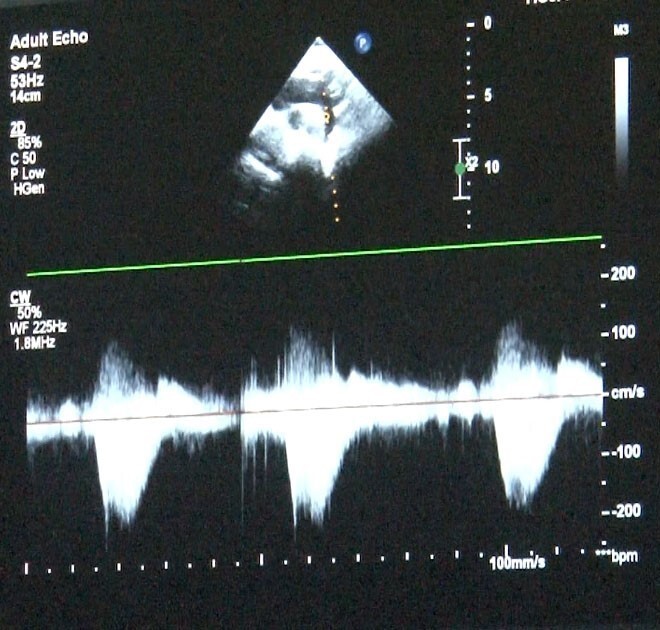

Uzman, gebelik sırasında fetal ekokardiyografi ile anne karnındaki bebeklerin kalp yapısının değerlendirilebileceğini ve erken tanı sayesinde doğum sonrası zamanında müdahale şansı yakalandığını vurguladı. Doğum sonrasında hızlı nefes alma, morarma veya emerken soğuk terleme gibi bulgular görüldüğünde çocuk hekimi tarafından çocuk kardiyoloğuna yönlendirmenin hayati önem taşıdığını belirtti.